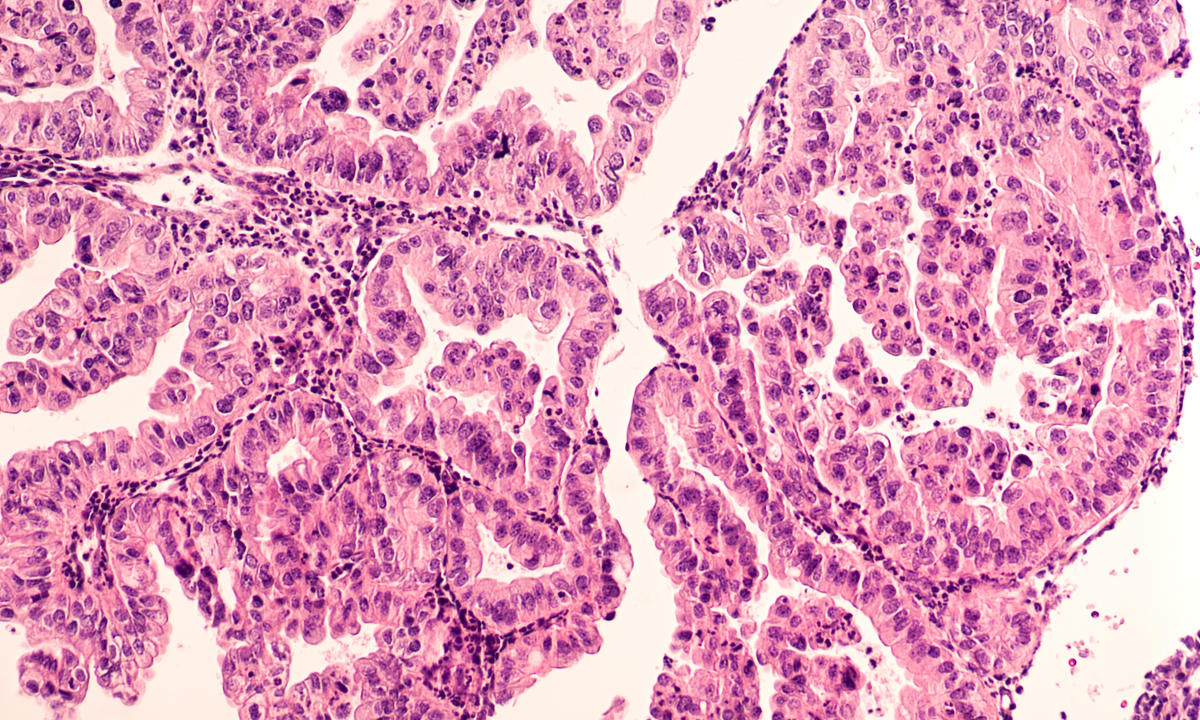

Catherine found out the hard way that her condition cannot be treated by diet and exercise. Disclaimer: This photo is not reflective of the article's content. Image Credit: Pexels/Thirdman